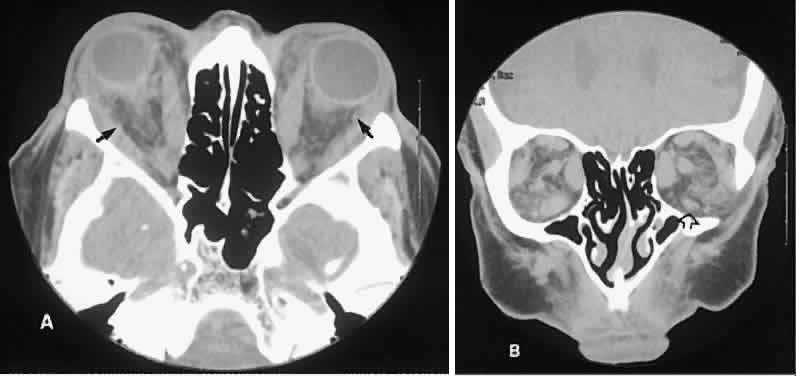

Graves' orbitopathy probably represents the most frequent cause of proptosis and EOM enlargement. The CT findings are fairly stereotyped and typically display various degrees of EOM enlargement (Fig. 7). The inferior rectus muscle usually is affected earliest, followed by the medial rectus, superior rectus, and finally the lateral rectus muscle. Rootman and colleagues13 noted more frequent involvement of the superior rectus/levator and medial rectus muscles than what had been reported previously with Graves' orbitopathy. These muscles can be affected in isolation, with the exception of the lateral rectus. To the best of our knowledge, isolated lateral rectus enlargement has not been reported in Graves' orbitopathy and in our experience usually is associated with a sphenoid wing meningioma.

Fig. 7. Graves' orbitopathy with two variations. Axial (A) and coronal (B) views show symmetric fusiform enlargement of the extraocular muscles with tapered muscle insertions. Note the predominant enlargement of the inferior, medial, and superior rectus muscles with lesser involvement of the lateral rectus muscle, a frequent pattern of enlargement in Graves' orbitopathy. Axial (C) and coronal (D) views of Graves' orbitopathy with expansion of retrobulbar ground substance and relative sparing of the extraocular muscles.

CT evidence of Graves' orbitopathy tends to be bilateral. Approximately 86% of patients with unilateral clinical findings have bilateral CT findings in our experience, which is consistent with the experience of others.42

Morphologically, the EOM belly is enlarged, with a gradual tapering toward and sparing of the tendinous portion of the muscle. Tendon involvement is a typical feature of orbital myositis. Tendon involvement helps to differentiate this lesion from Graves' orbitopathy, although Rootman and Nugent43 have noted a rare patient with Graves' orbitopathy with this finding.